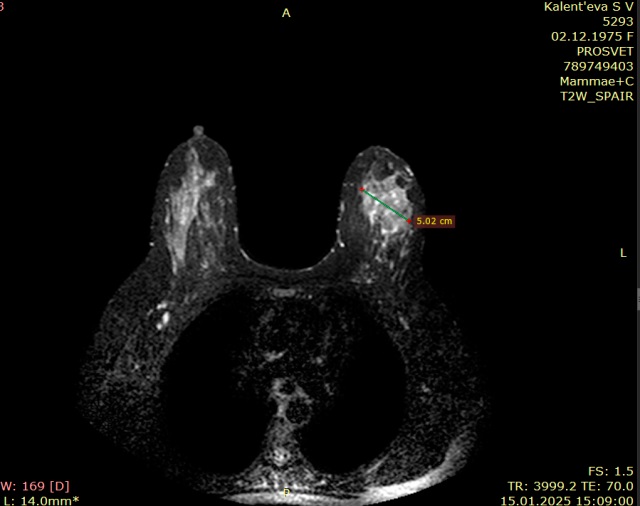

Мы проанализировали диагностические возможности совпадения размеров поражения 0 стадии РМЖ по данным МРТ/маммографии (рис. 3) и планового морфологического исследования.

Рисунок 3. МРТ молочных желез (в левой молочной железе зона контрастирования внутрипротокового рака)

Figure 3. MRI of the mammary glands (in the left mammary gland there is a contrast zone of intraductal cancer)

МРТ молочных желез выполнена у 49,1 % пациенток, при этом размеры поражения по данным маммографии и МРТ совпали в 53,7 % случаев, а при сравнении размеров поражения по МРТ и морфологического исследования и аналогичного сопоставления маммографии и морфологического исследования данные не различались (табл. 3). При этом средние размеры сancer in situ 42 мм по результатам планового гистологического исследования.

МРТ молочных желез при неинвазивном РМЖ — необходимый компонент для определения распространенности процесса, определения мультифокальности или мультицентричности поражения, и, как следствие, решения вопроса о возможности сохранения молочной железы или ее удаления.

При этом кроме обычного МРТ молочных желез с контрастом, по данным литературы, применяют многопараметрическую МРТ, и дополнительные методы позволяют исключить инвазивный компонент РМЖ [21].

Если сравнить цифровой томосинтез молочной железы с контрастным усилением с маммографией с контрастным усилением и МРТ молочных желез, то самая высокая чувствительность и точность на первом месте у МРТ молочных желез, на 2-м месте — томосинтез с контрастным усилением и на 3-м месте маммография с контрастом [22–25].